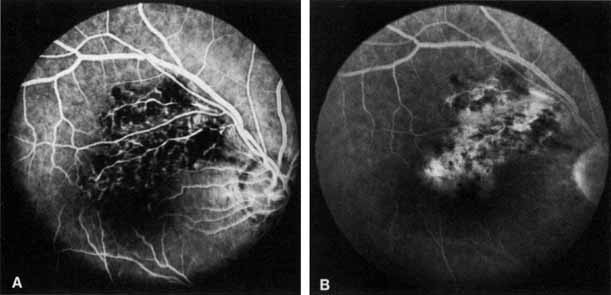

HEMICENTRAL AND HEMISPHERIC RETINAL VEIN OCCLUSION

The terms hemicentral, hemiretinal, and hemispheric retinal vein occlusion refer to eyes in which approximately half the venous outflow from the retina, either the superior or the inferior, has been occluded. In approximately 20% of eyes, the branch retinal veins draining the superior and inferior halves of the retina enter the lamina cribrosa separately before joining to form a single central retinal vein.175 Hemicentral retinal vein occlusion is an occlusion of one of these dual trunks of the central retinal vein within the nerve.176,177 Hemispheric retinal vein occlusion is an occlusion involving the venous drainage from approximately half of the retina, either the superior or the inferior retina (Fig. 7; see Fig. 11).75,178 This has also been referred to as a hemiretinal occlusion.362,363 In some eyes, the occlusion occurs in one of the dual trunks of the central retinal vein in which such a pattern exists (and then would qualify as a hemicentral retinal vein occlusion); the term hemispheric retinal vein occlusion actually includes the term hemicentral retinal vein occlusion.

Fig. 7 Equator-plus (A) and 30° photograph (B) of a hemispheric branch retinal vein occlusion.

In some eyes, the nasal retina is not drained by a separate vein, but by a branch of either the superior or the inferior temporal vein.179 It is the occlusion of one of these veins draining both the nasal retina and the superior or inferior retina near the optic disc that accounts for the majority of hemispheric retinal vein occlusions.75 In some eyes, however, it is impossible to determine the site of occlusion even with a good-quality fluorescein angiogram,75 and that is why we prefer the term hemispheric to describe this type of occlusion. The retinal area involved, appearance, clinical course, and complications from neovascularization are similar for both entities (see Table 2). The treatment and classification are similar to that of branch retinal vein occlusion.

The Eye Disease Case-Control Study reported the risk factors for a hemispheric or hemiretinal vein occlusion in a prospective study at five eye care centers.362 The three factors that were significantly associated with this type of occlusion compared to control were systemic hypertension, diabetes mellitus, and glaucoma. A reduction in risk with moderate alcohol consumption was noted, but it was not statistically significant, possibly because of the small number of cases (79) in this series.362 The study felt that there were more similarities than dissimilarities in the risk factor profiles for central retinal vein occlusion, branch retinal vein occlusion, and hemispheric or hemiretinal vein occlusion.362,363

We have seen one patient in whom a superotemporal branch retinal vein occlusion developed in the same eye with an inferior hemispheric retinal vein occlusion, producing the appearance of a three-quarter retinal vein occlusion.